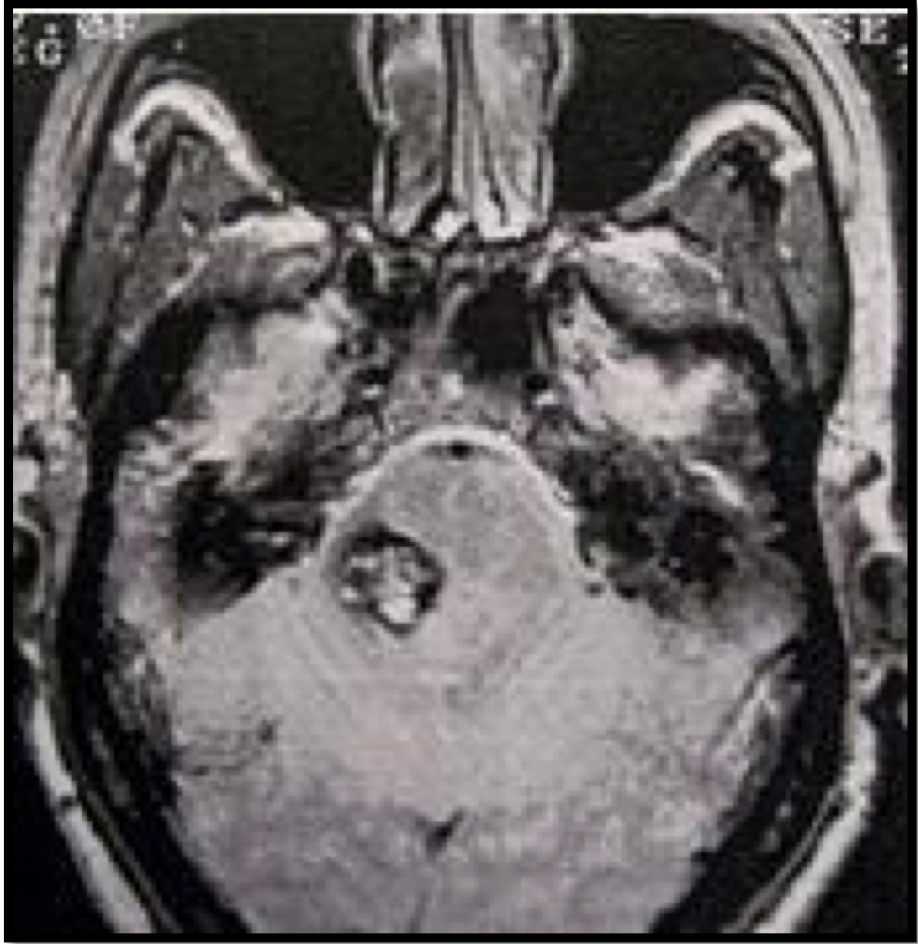

berikut ini adalah gambar dari penyakit…

A. Arteriovenous malformation (AVM)

B. Cavernous Hemangioma

C. CBM

D. Metastatic carcinoma

E. Tuberculoma

B